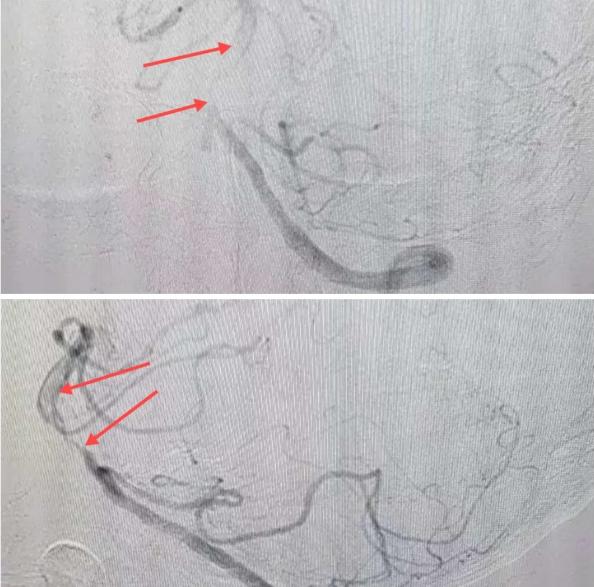

在經(jīng)造影后,主刀醫(yī)生腦一科副主任楊慶堂發(fā)現(xiàn)患者基底動脈下段重度狹窄且狹窄段以遠有大負(fù)荷血栓,其狹窄處考慮為動脈夾層,手術(shù)難度及風(fēng)險較大。楊慶堂副主任在彭壯副主任醫(yī)師的協(xié)助下運用spaceman(太空人)技術(shù),中間導(dǎo)管抵近血栓抽吸配合支架拉栓,成功開通血管。再次造影可見基底動脈管腔明顯增寬,遠端血管顯影良好,且等待20分鐘后造影仍顯示血流通暢。楊慶堂副主任考慮到本次手術(shù)時間不宜過長,現(xiàn)患者基底動脈及分支前向血流維持良好,給予其抗栓藥物應(yīng)用后結(jié)束手術(shù),并建議患者3個月后復(fù)查造影,明確其基底動脈夾層情況。

造影可見血管夾層和大量血栓形成

取栓后血管管腔增寬,前向血流良好